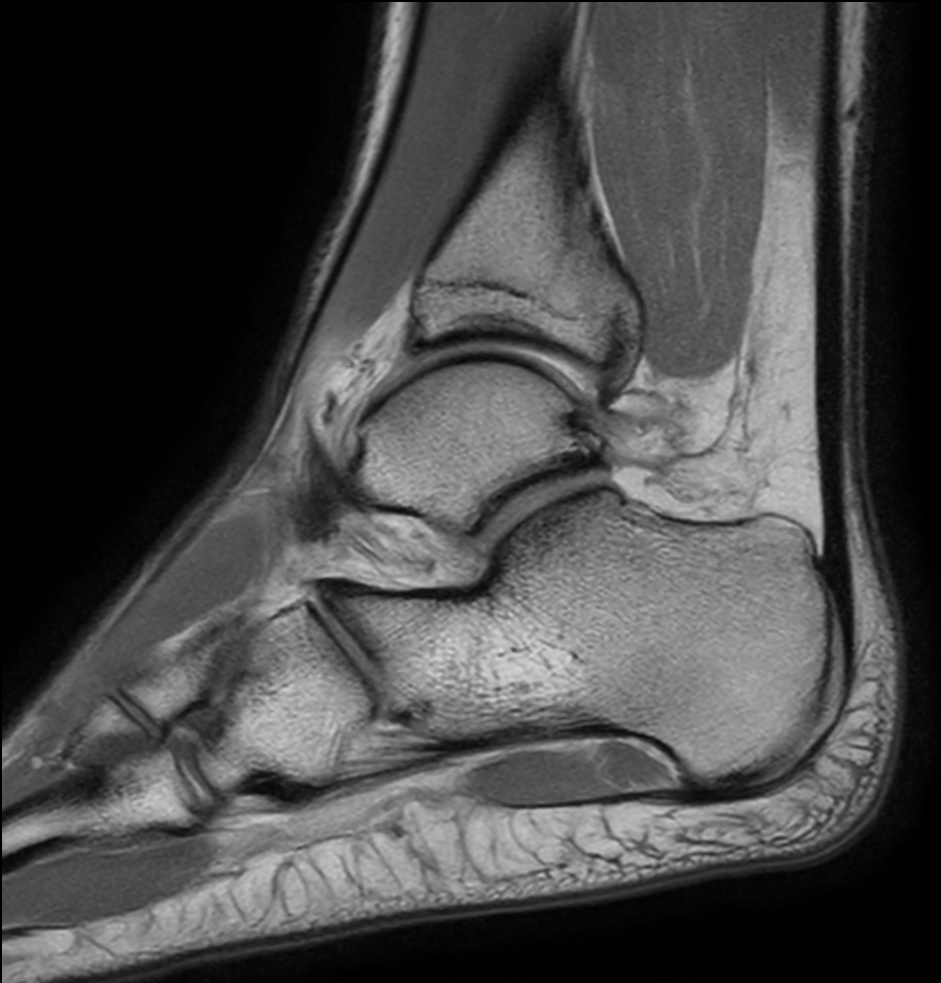

Sagittal T1w TSE